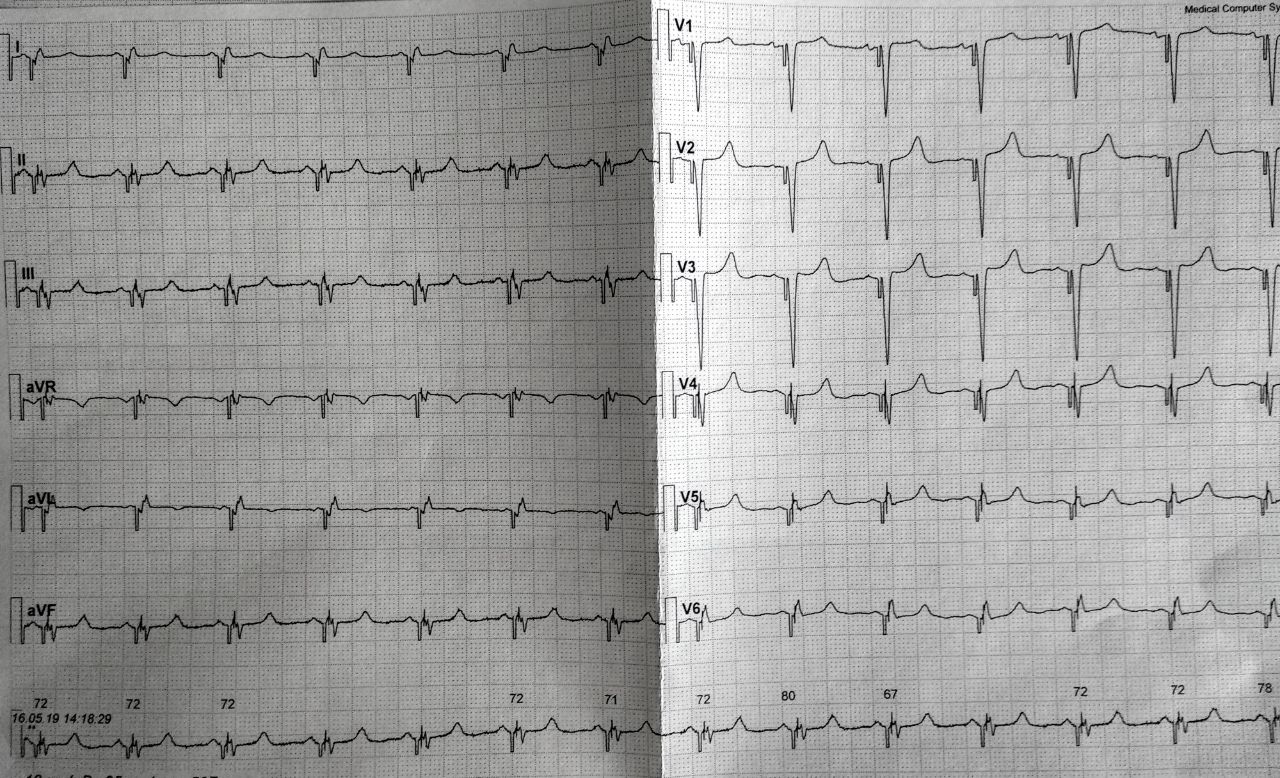

В 2012г впервые описана ПБЛНПГ на ЭКГ, на эхо-КГ патологии не выявлено.